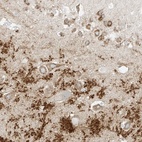

Immunohistochemical staining of human hippocampus shows strong cytoplasmic positivity in neuronal cells and processes.